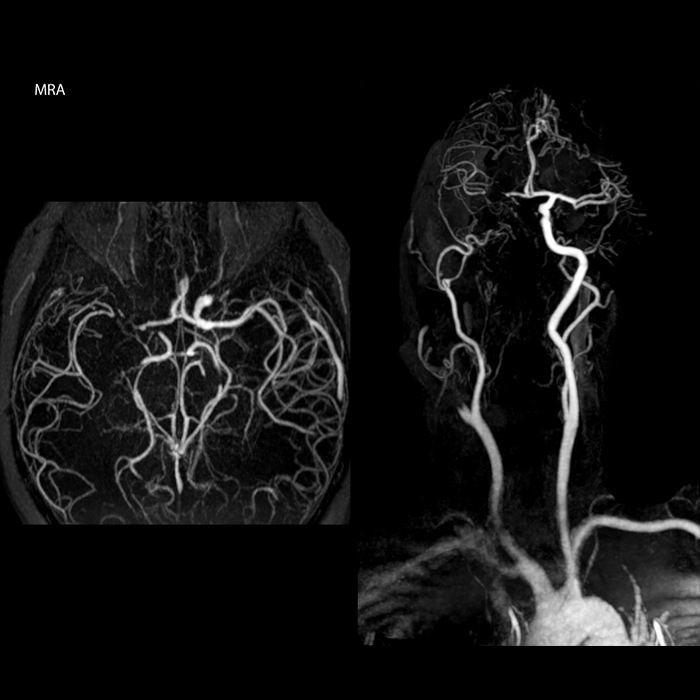

“In France, every stroke is usually imaged with MRI, not CT, even for emergency treatment.” “In France, stroke is usually imaged with MRI, not CT, even for emergency treatment. This is because MRI helps us directly visualize ischemia in the acute phase, but can also help rule out differentials such as MS and hematoma. In addition, we can assess the intracranial and extracranial vessels during the same examination,” says Dr. Savatovsky.

“Ingenia provides great flexibility in the parameters setting. We can tune a sequence the way we want,” says Dr. Savatovsky. “For example, in a stroke exam we use a FLAIR sequence of about two minutes instead of the four-minute FLAIR we use for MS. The diffusion is 30 seconds, the T2*-weighted scan is 30 seconds, the angiography scan time is less than one minute. Ingenia is a great scanner in that situation; even with these fast sequences we can achieve good images with good SNR. When the first sequence tells us that it’s not an ischemic stroke but a hemorrhagic stroke, we may switch to a time-resolved angiography to look for vascular malformations and venous thrombosis.

“Every center is different, but for me the ideal protocol for stroke includes diffusion weighted imaging, FLAIR, and fast susceptibility imaging,” says Dr. Savatovsky. “Our fast susceptibility weighted imaging takes 50 seconds, so it’s as fast as T2*-weighted imaging. It visualizes hemorrhage but also the clots. We also do 3D MR angiography that provides information on cervical and brain vessels. If the patient does not need immediate treatment, or if additional information is needed to decide on treatment, we might also add perfusion imaging and post-contrast T1-weighted imaging.”